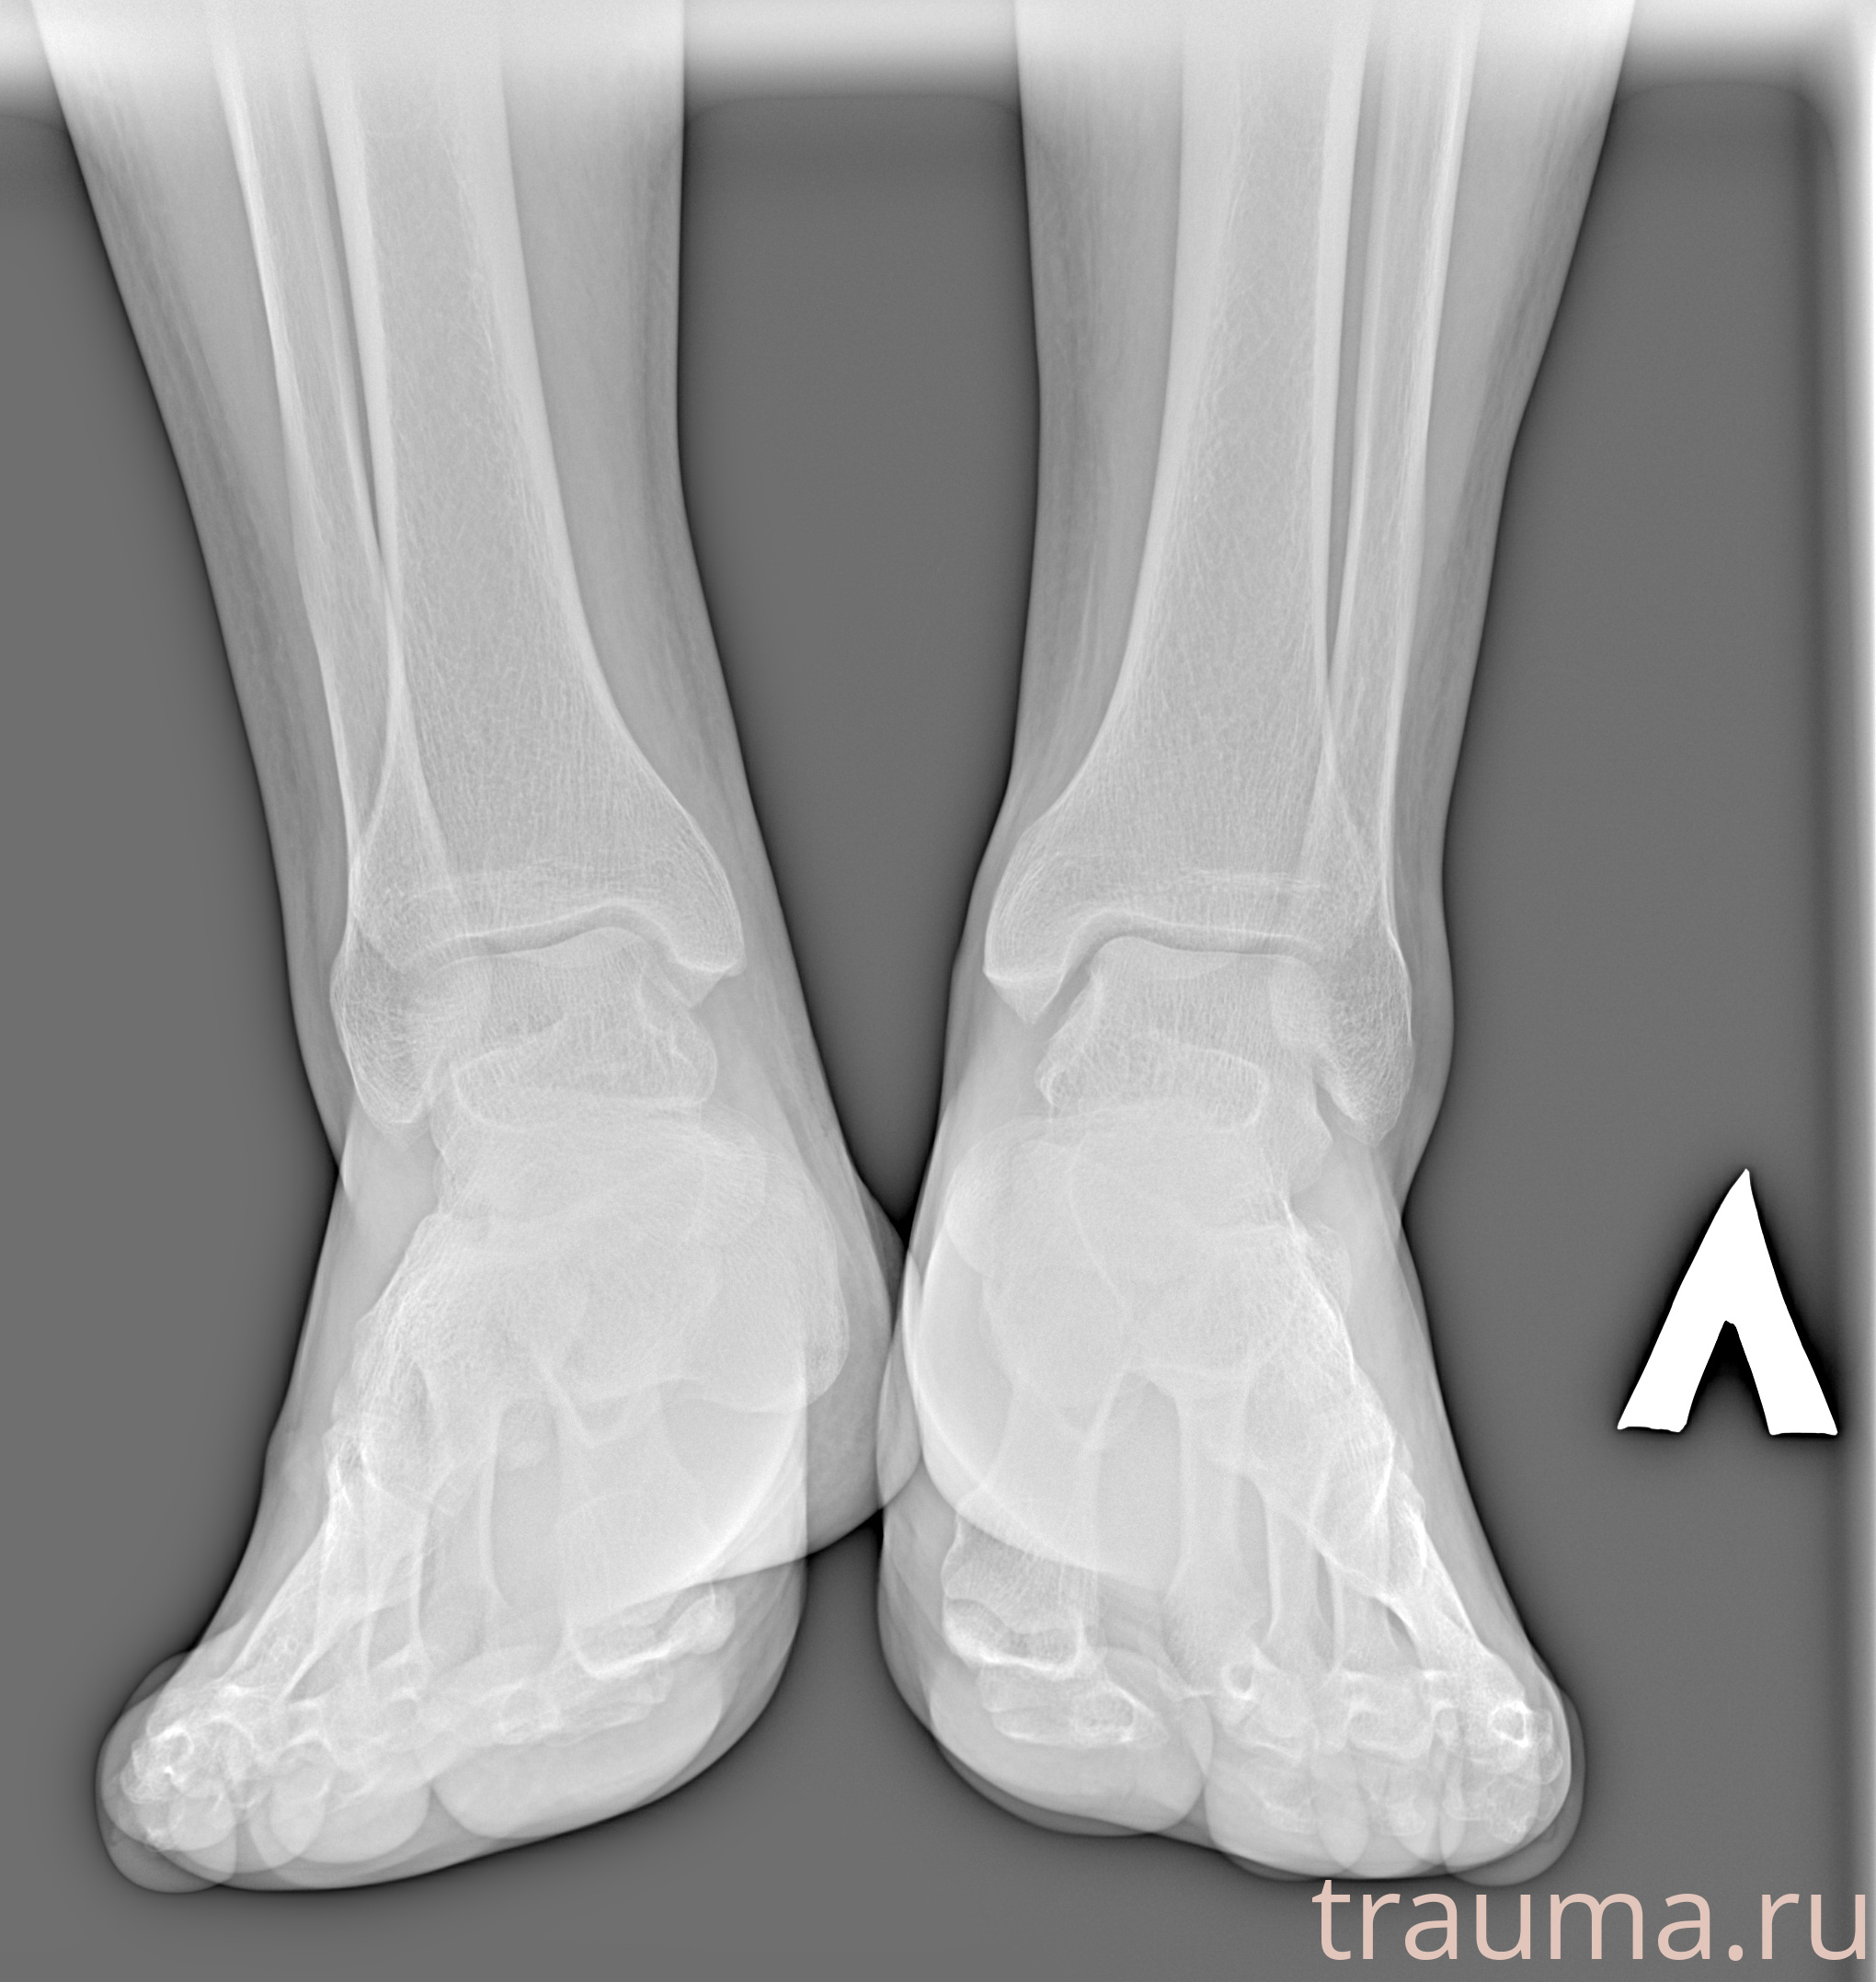

Рентгенограммы

Рентген на дому: по вашему адресу приезжает врач-рентгенолог, травматолог-ортопед с мобильным рентгеновским аппаратом, проводит диагностику травмы или заболевания, делает необходимые рентгенограммы, дает рекомендации по дальнейшему лечению. Получить качественные снимки в домашних условиях возможно благодаря уникальной методике, разработанной МосРентген Центром для института  Склифосовского